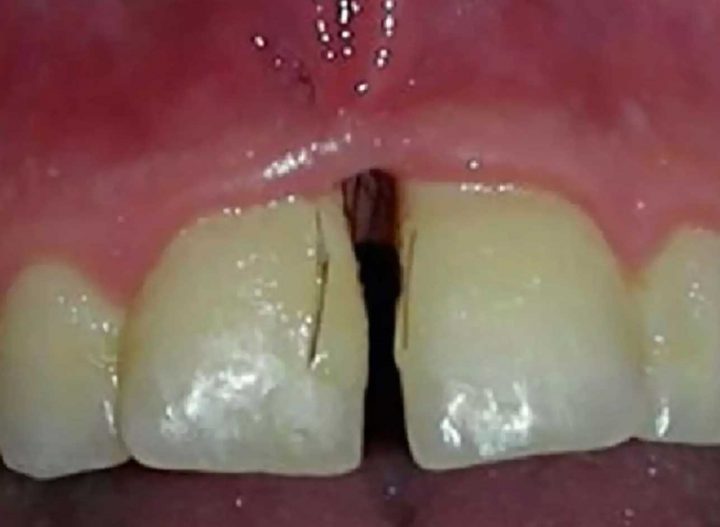

Le journal médical Oral Surgery, Oral Medicine, Oral Pathology and Oral Radiology rapporte un cas extrême d’hirsutisme assez particulier. Une jeune femme de 25 ans, atteinte du syndrome des ovaires polykystiques a remarqué la pousse de poils entre les dents. L’une des conséquences de ce syndrome, qui entraine un dérèglement hormonal est la pousse inhabituelle des poils. Mais un tel cas de poils aux dents est vraiment rare. « En examinant son visage on peut remarquer la présence d’une pilosité inhabituelle au menton et dans la zone du cou », peut-on lire dans l’article médical. « Un examen buccal révèle la présence de poils bruns, semblables à des cils ». Des photos de l’examen accompagnent l’article.

Des poils, tels des cils, ont poussé dans ses gencives

Les poils « ont été enlevés et les tissus ont été analysés. Un an plus tard, la patiente est revenue avec la présence encore plus importante de poils autour des gencives et dans les sillons gingivaux. » Ce genre de pathologie serait extrêmement rare. La cause de la présence de poils dans cette zone du corps est encore inconnue. « Une étude de cas précédents révèle cinq autres cas, mais la plupart indiquaient seulement la présence d’un seul poil à différents endroits de la cavité buccale ».